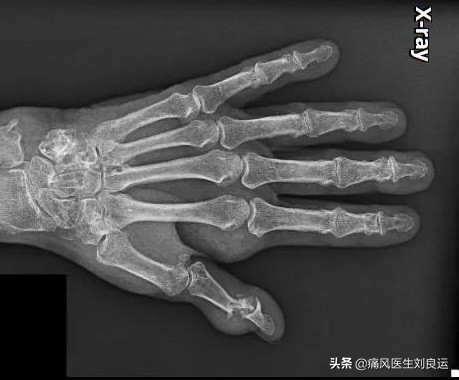

X线显示患者的指间关节骨质破坏,穿凿样骨质破坏,破坏的边缘骨质翘起